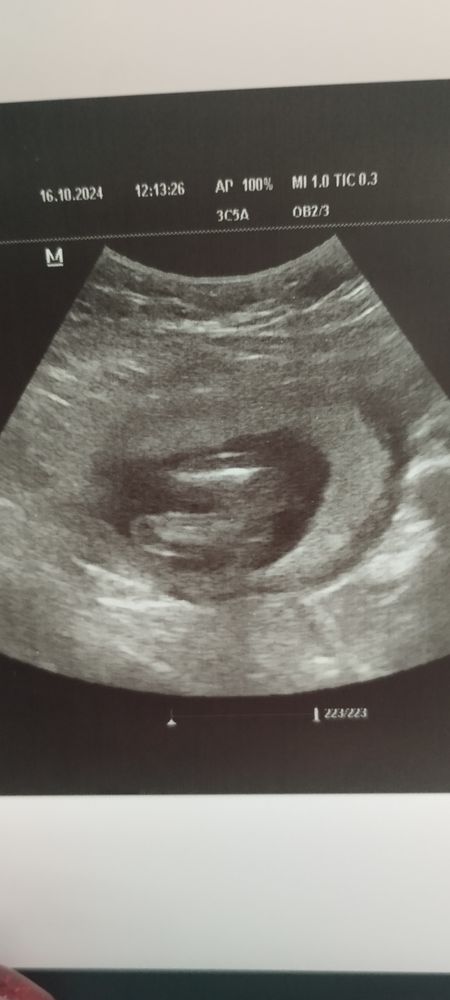

УЗИ в 16.2 недель. На кого похож?

Я с дочкой ходила на УЗИ контрольное в 17 нед, такая же картинка была) поздравляю🎉

Ну вроде да, девочка

Девочка)) поздравляю 💝